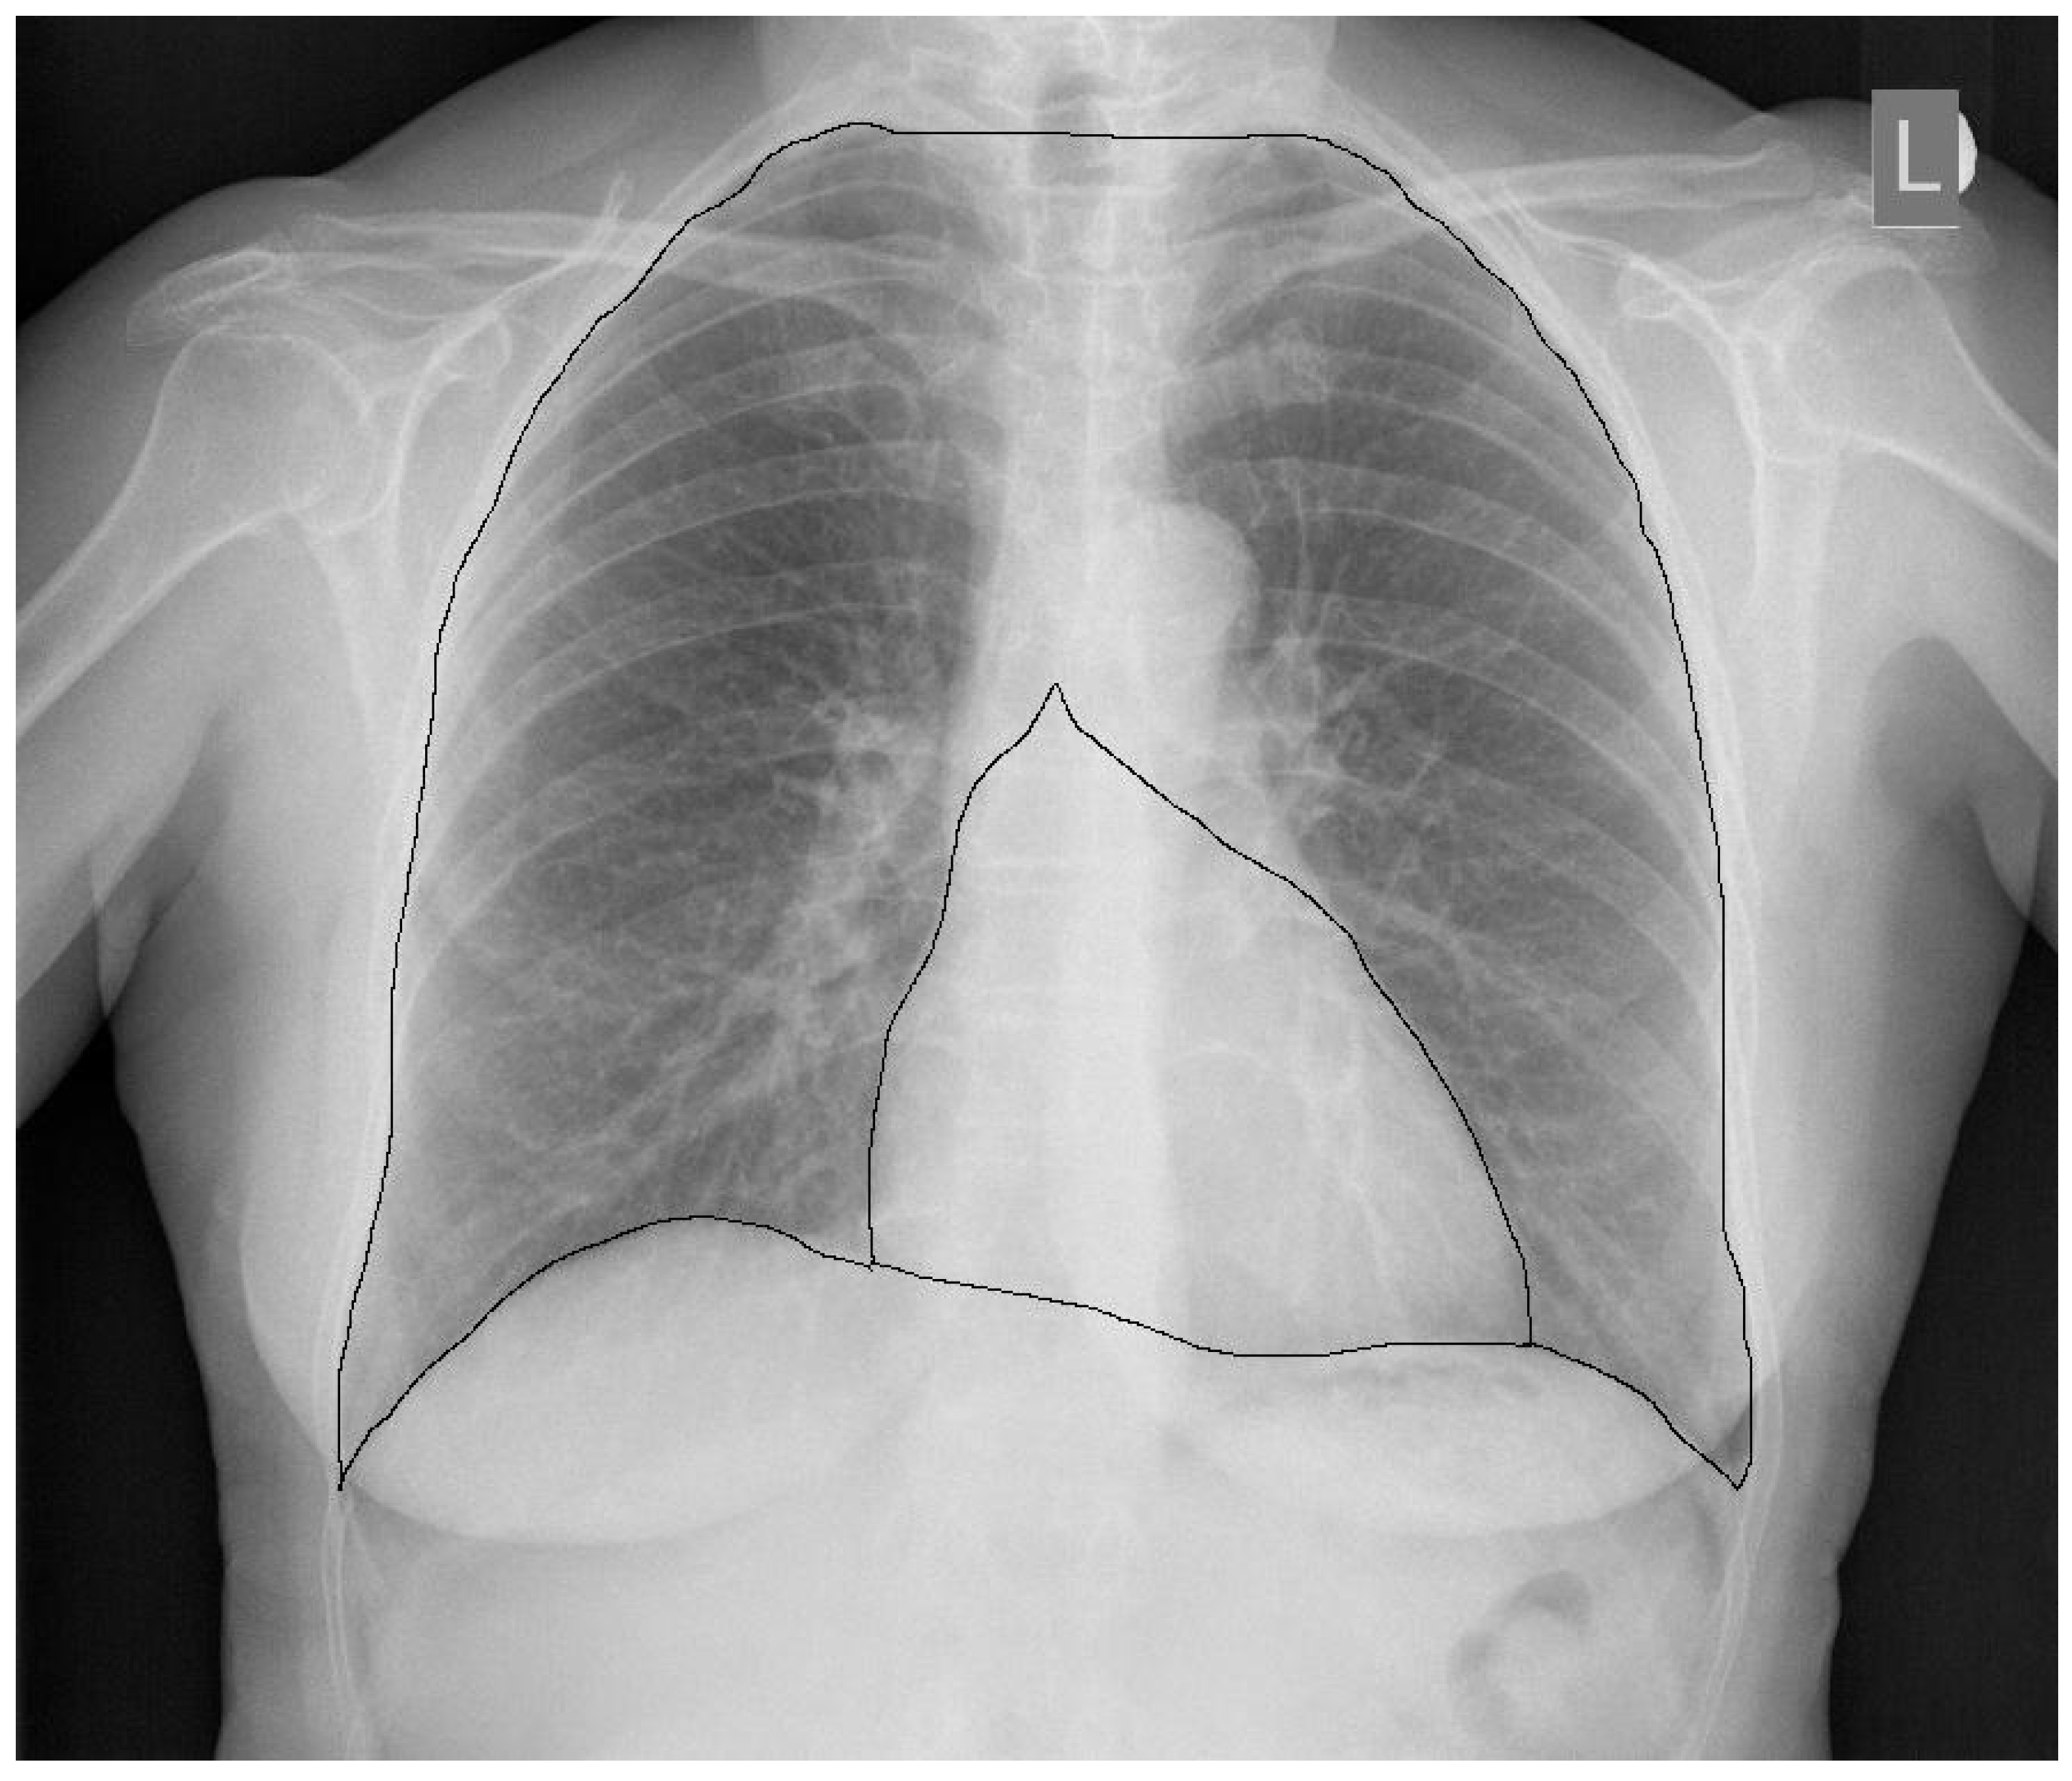

2. CTR—The Importance of Radiograph Projection